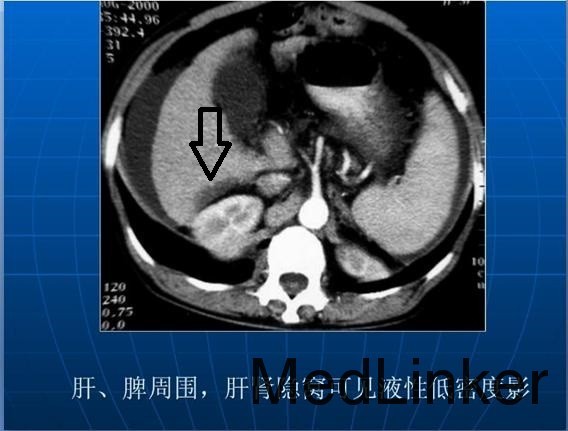

发一个肝肾隐窝积液的片子。

肝肾隐窝腹水查因